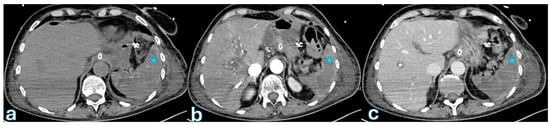

3. Biliary Leakage

The International Study Group of Liver Surgery (ISGLS) defines biliary leakage after pancreaticoduodenectomy as a drain fluid bilirubin concentration that is at least three times higher than plasma bilirubin levels, measured on or after the third postoperative day [96,97]. This condition can occur in as many as 8% of cases [16,20,98]. Although biliary fistulas are less frequent than postoperative pancreatic fistulas and are linked to a reduced risk of complications and death, they can nevertheless result in secondary complications, especially the formation of an intra-abdominal abscess, which may call for further treatments [21,41,99,100]. The primary risk factors for biliary leakage include excessive dissection of the hepatic duct (“skeletonization”), which can compromise vascular supply and healing; a small bile duct diameter, which increases anastomotic tension and impairs healing potential; and anastomosis involving the common bile duct, which presents technical challenges in maintaining an adequate seal [62,101,102,103]. To minimize these risks, several protective strategies have been developed, including refined reconstruction techniques to enhance anastomotic integrity, percutaneous biliary drainage to divert bile and promote fistula closure, and intraoperative T-tube placement to provide controlled bile drainage and reduce anastomotic stress [29,104,105,106,107]. In cases of biliary leakage, fluid collections are typically observed near the choledochojejunostomy, requiring cross-sectional imaging for accurate assessment [108,109,110]. On contrast-enhanced computed tomography (CECT), biliary leakage appears as homogeneously hypoattenuating fluid collections, generally without a well-defined capsule [4,46,111,112] (Figure 1).

On MRI, T1-weighted imaging (T1WI) demonstrates hypointense collections, while T2-weighted imaging (T2WI) shows hyperintense fluid accumulations, consistent with bile extravasation [113,114]. One of the main diagnostic challenges in imaging biliary leakage is differentiating it from a pancreatic fistula, given the close anatomical relationship between the choledochojejunostomy and pancreaticojejunostomy. Since both complications can present with fluid collections in similar locations, clinical correlation and biliary-specific imaging techniques are crucial for accurate diagnosis. Magnetic resonance cholangiopancreatography (MRCP) with HBAs can help in distinguishing these conditions [115,116]. By administering HBAs and acquiring images during the hepatobiliary phase (HBP), it is possible to directly visualize active bile leakage, as the contrast extravasates into the fluid collection, confirming a biliary origin HBA [117]. Since HBAs do not fill the pancreatic duct, the absence of contrast in the pancreatic region further differentiates it from a pancreatic fistula [48,118]. Studies have demonstrated that HBP-enhanced MRI using Gd-EOB-DTPA, when combined with MRCP, significantly improves diagnostic accuracy in detecting biliary leaks [119,120]. Compared to MRCP alone, this combined approach has shown an accuracy of 84%, a specificity of 100%, and a statistically significant improvement (p < 0.05) in diagnostic performance [121,122,123]. These findings emphasize the importance of HBP-enhanced MRI in optimizing the detection and characterization of biliary leaks, thereby improving the management of postoperative complications.